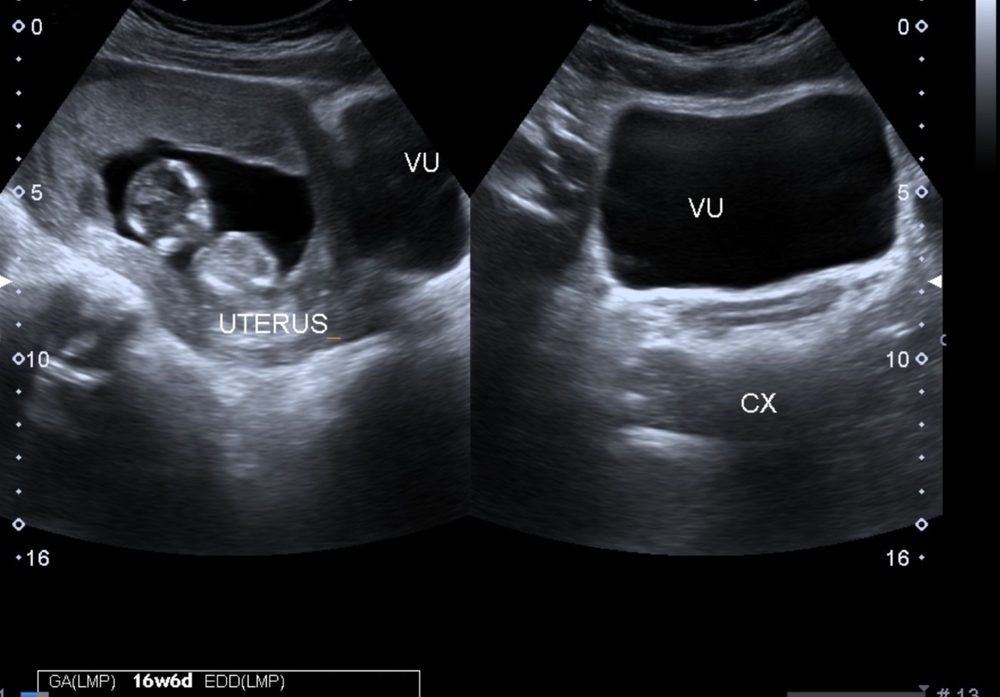

الرحم قد تمتص أحدهما ومحبات الألبان أكثر عرضة.. 14 معلومة مشوقة عن الحمل في توأم

يعتبر الحمل في توأم نعمة مزدوجة، لكنه قد ينطوي أيضاً على مخاطر أكبر من الحمل المفرد. وعلى الرغم من أنك...

ماذا يعني عدم ظهور كيس الحمل في اختبار الموجات فوق الصوتية، وماذا إذا كان فارغاً؟

بعد إجراء اختبار الحمل المنزلي، وتأكيده باختبار الدم، تبدأ الحامل سلسلة اختبارات أخرى مثل اختبار الموجات فوق الصوتية لرؤية الرحم...

لا يبدأ من أول يوم في الحمل كما قد يتصور البعض.. متى نسمع نبض الجنين؟ ولماذا قد يتوقف أو يتقطع؟

بالنسبة للأمهات الجديدات في أول تجربة ولادة يكون لديهن الكثير من التساؤلات تبدأ حتى من قبل معرفة الحمل، ومع أول...